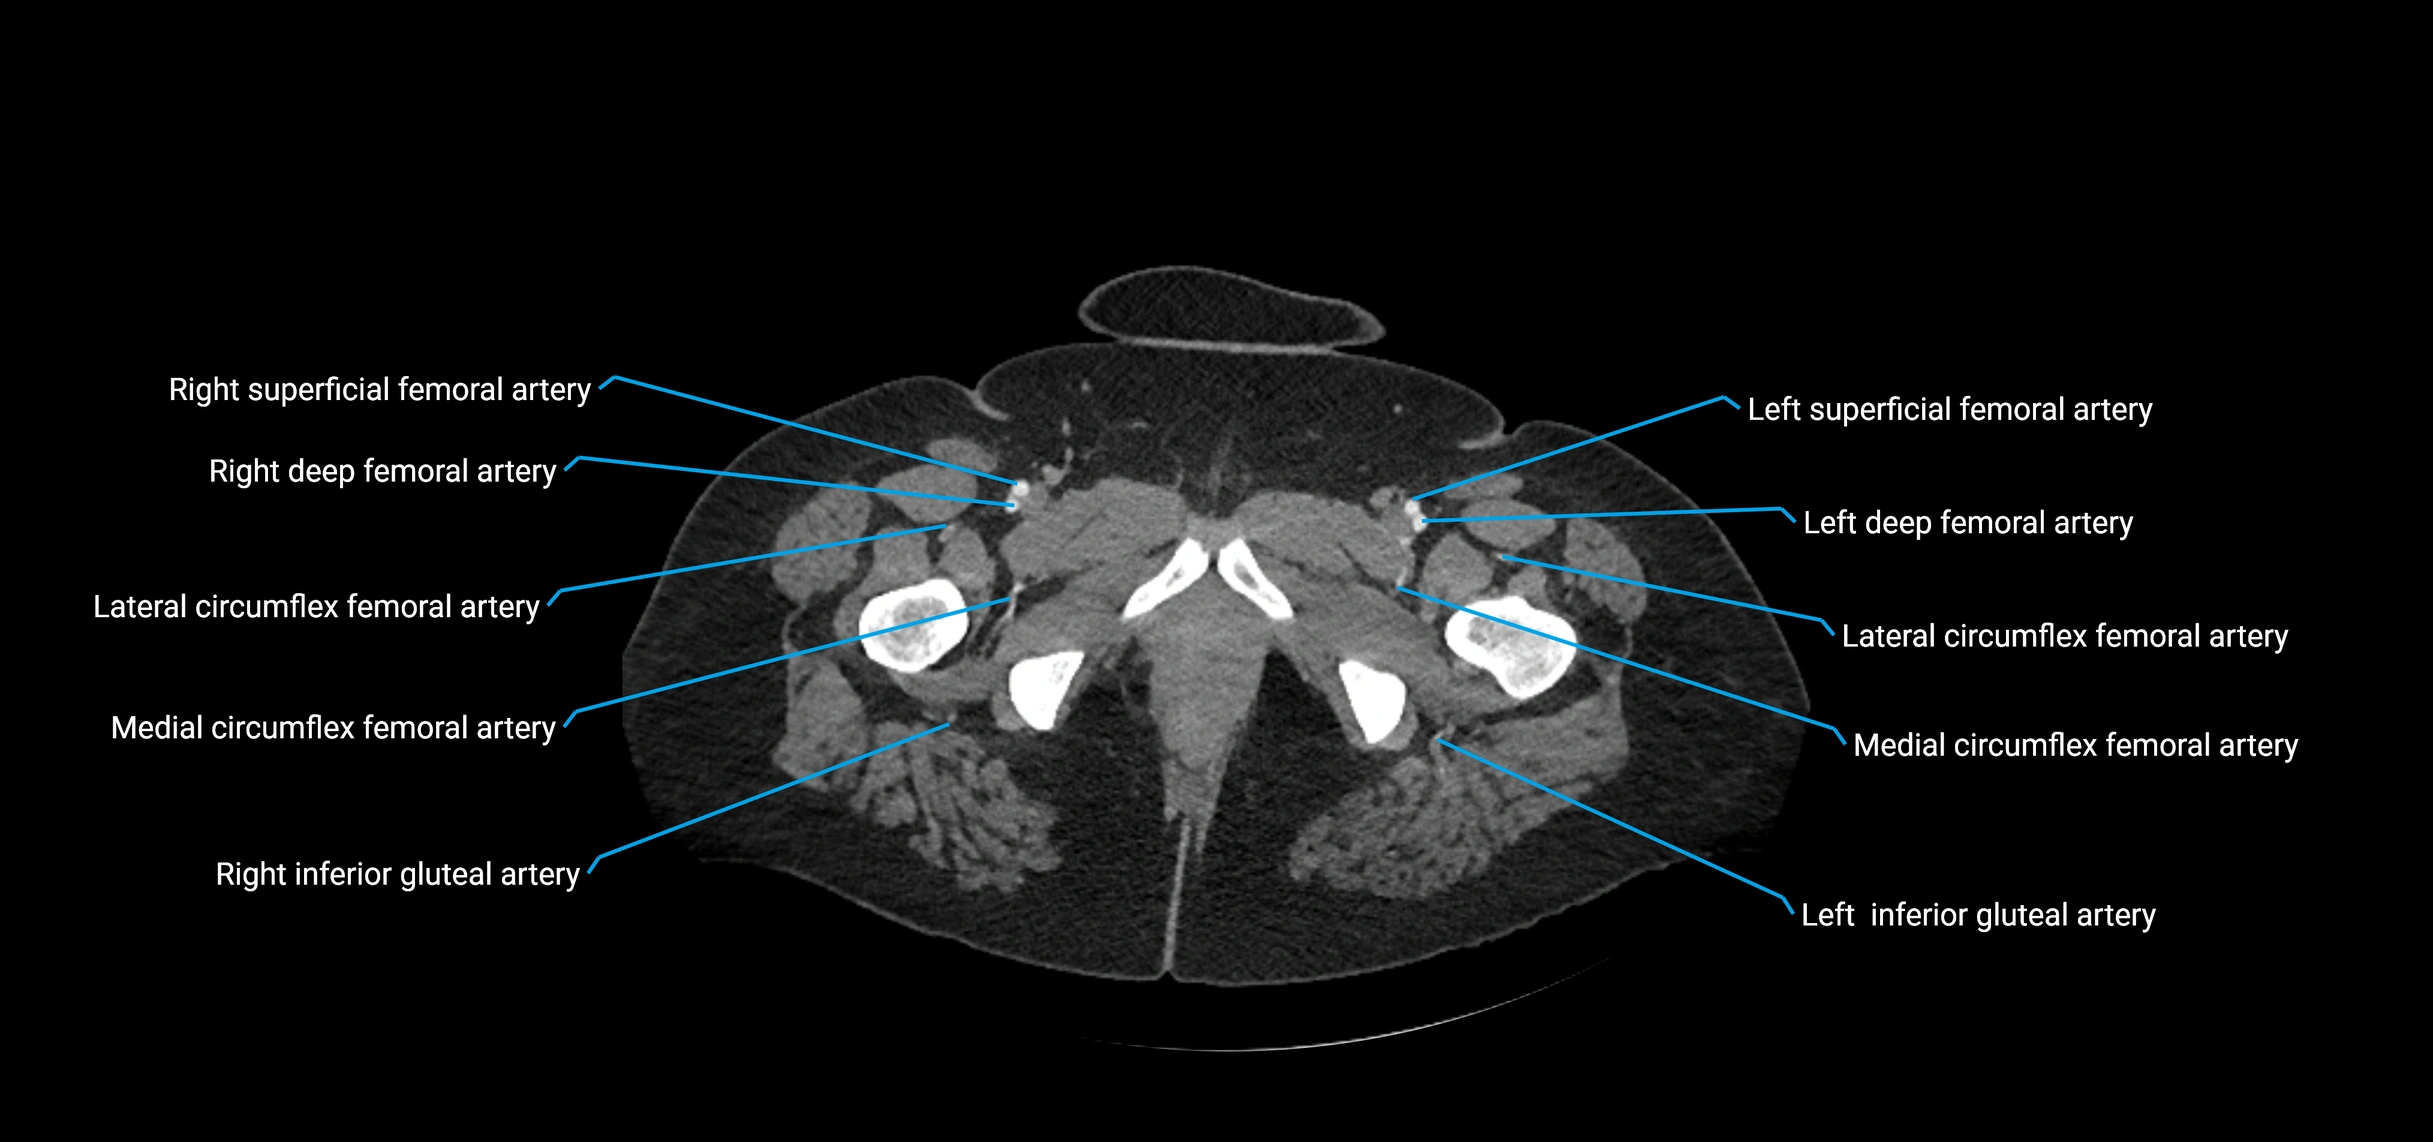

Contrast-enhanced CT (CTA):

• Gold standard for abdominal aortic imaging

• Provides excellent detail of lumen, wall, aneurysm, thrombus, and branch vessels

• Multiplanar and 3D reconstructions help in aneurysm measurement, stent graft planning, and dissection evaluation